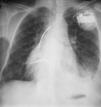

A 56-year-old man had been referred to our department in 1978 at age 22 with a diagnosis of congenital cyanotic heart disease, and had undergone ventricular (VSD) and atrial septal defect (ASD) closure and repair of pulmonary valve stenosis. The chest X-ray showed mesocardia. He began to experience signs and symptoms of heart failure in 1992, with a systolic murmur audible over the left sternal border. Serial transthoracic echocardiography (TTE) showed a residual high VSD. Cardiac magnetic resonance imaging (MRI) in 1999 detected transposition of the great vessels but no VSD or ASD.

In 2005, the patient received an implantable cardioverter-defibrillator (ICD) due to syncopal ventricular tachycardia (Figure 1).